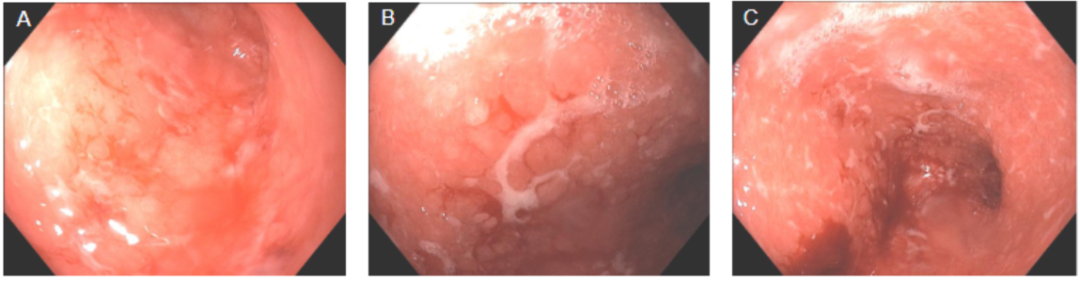

- 【论著】粪钙卫蛋白在溃疡性结肠炎内镜活动度评估中的价值及与常用炎症指标的比较分析 溃疡性结肠炎(ulcerative colitis,UC)是一种慢性复发性的肠道炎性疾病。随着 UC 的疾病进展,患者常出现营养不良、贫血等并发症,严重影响患者的生活质量。……